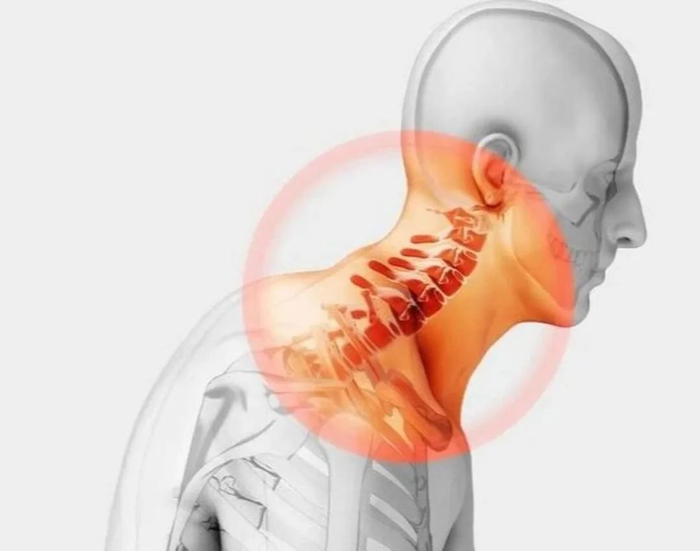

颈椎病又称颈椎综合症,由于人体颈椎间盘逐渐地发生退行性变、颈椎骨质增生或颈椎正常生理曲线改变后刺激并压迫颈神经根、颈部脊髓、椎动脉、颈部交感神经而引起的一组综合症状 颈椎病症状较多,如颈部出现不适感、疲劳感,然后反复的落枕,或是经常出现头晕头疼,手臂酸痛无力、麻木,失眠心烦,恶心呕吐。

,这些都有可能和颈椎病有关如果特别严重的话,甚至可能出现走路不稳,脚步虚浮等症状 颈椎病的易发人群分两类,一就是在生活工作中长期伏案低头的人群,如办公室一族、教师、司机、学生等,因长期低头伏案使颈椎长期处于非生理性体位,颈部肌肉也长期处于紧张状态,从而使颈部肌肉及相应韧带等软组织累积性损伤。

颈椎病大致分为7种类型,其中最常见的是颈型颈椎病,症状相对来说比较轻,主要出现颈肩部僵硬不适、疼痛,严重的会引起反复的落枕针对此类型的颈椎病,中医的治疗方法会相对更多,如理疗、推拿、针灸等都有较好疗效。

第二种类型为椎动脉型颈椎病,椎动脉型颈椎病主要引起的是头晕,视线模糊,部分人还会影响记忆力,出现一过性记忆力减退 第三种类型为神经根型颈椎病,主要影响神经系统,会出现手麻、握力减退、上肢无力以及发凉发冷的现象。

第四种类型是交感神经型颈椎病,此类型症状多样,如心慌、心律不齐、眼干、血压不稳等 第五种为食管压迫型颈椎病,会有咽部异物感,吞咽困难等症状,这是由于颈部骨质增生压迫食管导致的 第六种也是最严重的一种类型就是。

脊髓性颈椎病,会使患者走路无力,脚步虚浮。 最后一种就是混合性颈椎病,可能出现上述多种症状。